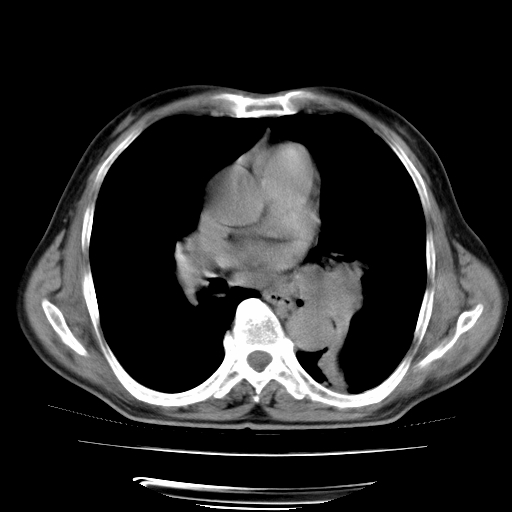

男,71岁,咳嗽,气喘10年,再发并咯血.胸片见气胸

考虑  左肺中心型肺癌伴阻塞性肺炎,肺不张,纵膈淋巴结肿大。慢支炎,肺气肿,左侧气胸肺压缩5%

左侧中央型肺癌伴纵膈淋巴结转移。

左肺中心型肺癌伴阻塞性肺炎,肺不张,纵膈淋巴结肿大

1)考虑左肺中心型肺癌伴阻塞性肺炎、左肺下叶肺不张、左侧肺气肿,纵膈淋巴结转移。2)左侧气胸(肺组织压缩约5%)。

左肺中心型肺癌伴阻塞性肺不张、肺气肿 。

1)考虑左肺中心型肺癌伴阻塞性肺炎、左肺下叶肺不张、左侧肺气肿,纵膈淋巴结转移。2)左侧气胸。